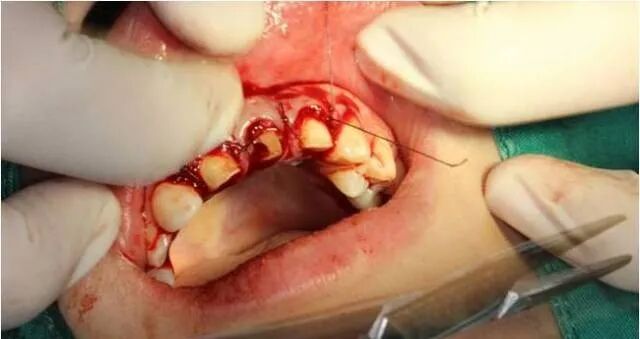

翻瓣后清除炎性组织

颈缘骨修整

软组织修复整

间断缝合

基牙备置